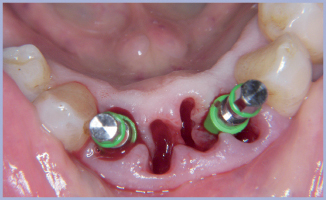

Dalla seconda chirurgia si passava alle impronte (fig. 15) al fine di realizzare una riabilitazione in zirconia grazie all’uso del CAD/CAM.

Gli abutments venivano scelti direttamente in bocca e verificati sul modello grazie al kit monconi di prova Exacone® 360° (fig. 16).

La scansione del modello consentiva la realizzazione di un cast verification index, utile ai fini della verifica della corrispondenza tra la posizione degli abutment sul modello ed in bocca (figg. 17-18).